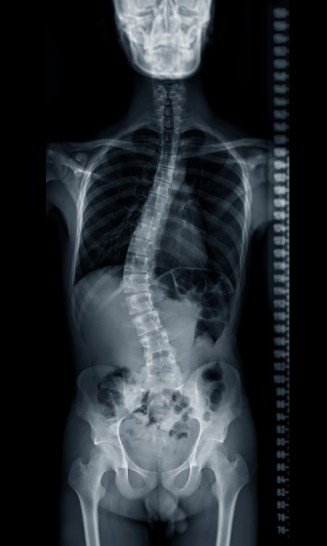

La escoliosis es una condición en la que la columna vertebral se curva de manera anormal hacia los lados, formando una especie de “S” o “C” cuando se observa de frente o de espaldas. Aunque muchas personas piensan que se trata solo de una mala postura, en realidad es una alteración estructural que puede avanzar con el tiempo y afectar tanto la estética corporal como el funcionamiento interno, dependiendo de su gravedad.

Existen distintos grados de escoliosis: en algunos casos es leve y apenas perceptible, mientras que en otros puede llegar a generar dolor, rigidez muscular, fatiga y hasta problemas respiratorios cuando comprime los pulmones. Lo más importante es saber que no todas las curvaturas requieren cirugía; sin embargo, en los casos más severos o progresivos, los especialistas consideran la intervención quirúrgica como la mejor forma de corregir la deformidad y prevenir complicaciones a largo plazo.